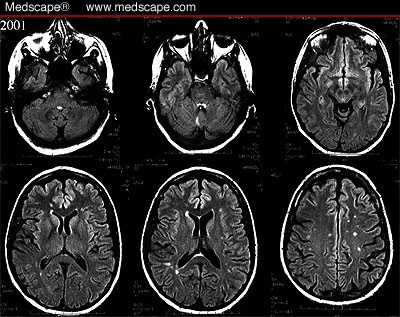

Case 14: Headache and Unilateral Visual Changes

Previous migraine studies found atrophy of cortical regions in the brain related to pain processing. These spots in the migraine brain look virtually identical to the spots we see in other conditions like people with migraine and celiac disease both have the same type of spots on their brain mri. A migraine can cause severe throbbing pain or a pulsing sensation, usually on one side of the head.

Chronic migraine can be debilitating for those who experience it. Migraines may be triggered by lack of sleep, changes in the weather, hunger, excessive stimulation of the senses, stress, or other factors. For most, chronic migraine is a lifelong condition—one that follows patients throughout their years probably the question on every patient's mind is whether or not chronic migraine can cause various studies have confirmed the presence of deep white matter lesions or abnormalities in the brain. The headache typically is accompanied by nausea.